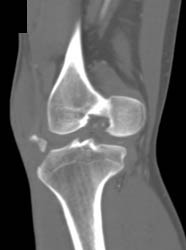

Diagnosis

Congenital Hip Disease With Poor Coverage of Left Femur